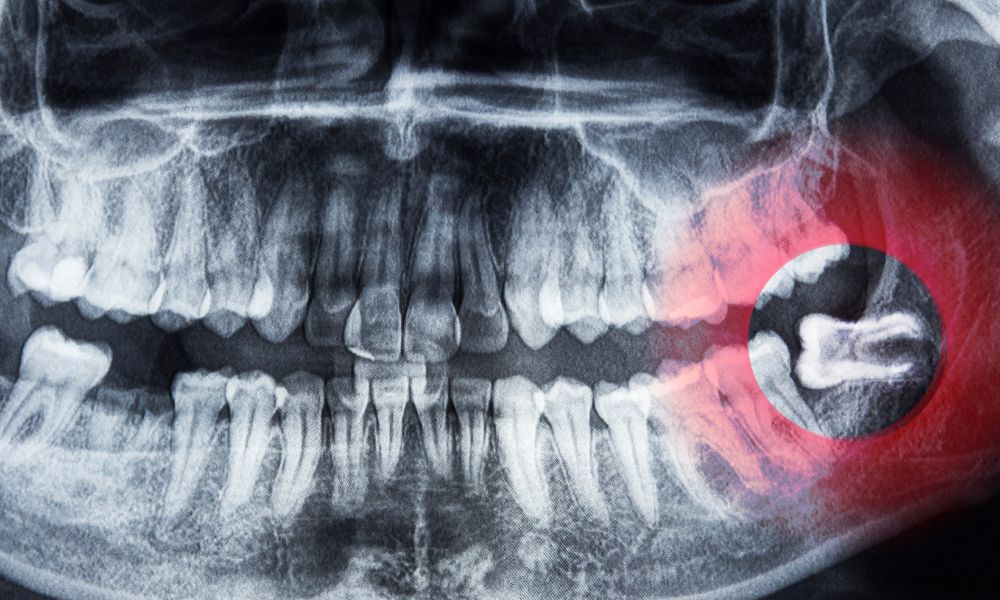

Radiografías y Otras Pruebas de Imagen

Una radiografía panorámica puede proporcionar una visión completa de todos los dientes a la vez, lo que ayuda a guiar la extracción de las muelas del juicio. Estas imágenes muestran la relación de las muelas del juicio con otros dientes, los senos paranasales y los nervios, lo que ayuda a planificar el procedimiento de extracción.